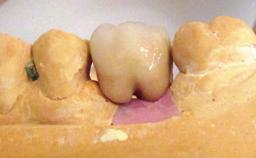

A 30-year-old female patient was referred to the Department of Periodontology of the University of Bern, Switzerland, by a dentist in private practice. Tooth 45 had been congenitally missing and had been replaced with a titanium implant three years prior to the first visit at the Department of Periodontology. The tissue level implant had a diameter of 4.1 mm, a length of 12 mm, and a sandblasted and acid-etched (SLA) surface (Straumann® Dental Implant System; Institut Straumann AG, Basel, Switzerland). The metal-ceramic crown on implant 45 had been cemented permanently. Implant 45 had been diagnosed with peri-implantitis by the referring dentist in the course of regular supportive care.

Retention Cemented, with prosthesis margin < 3mm submucosal Cemented, with prosthesis margin < 3mm submucosal